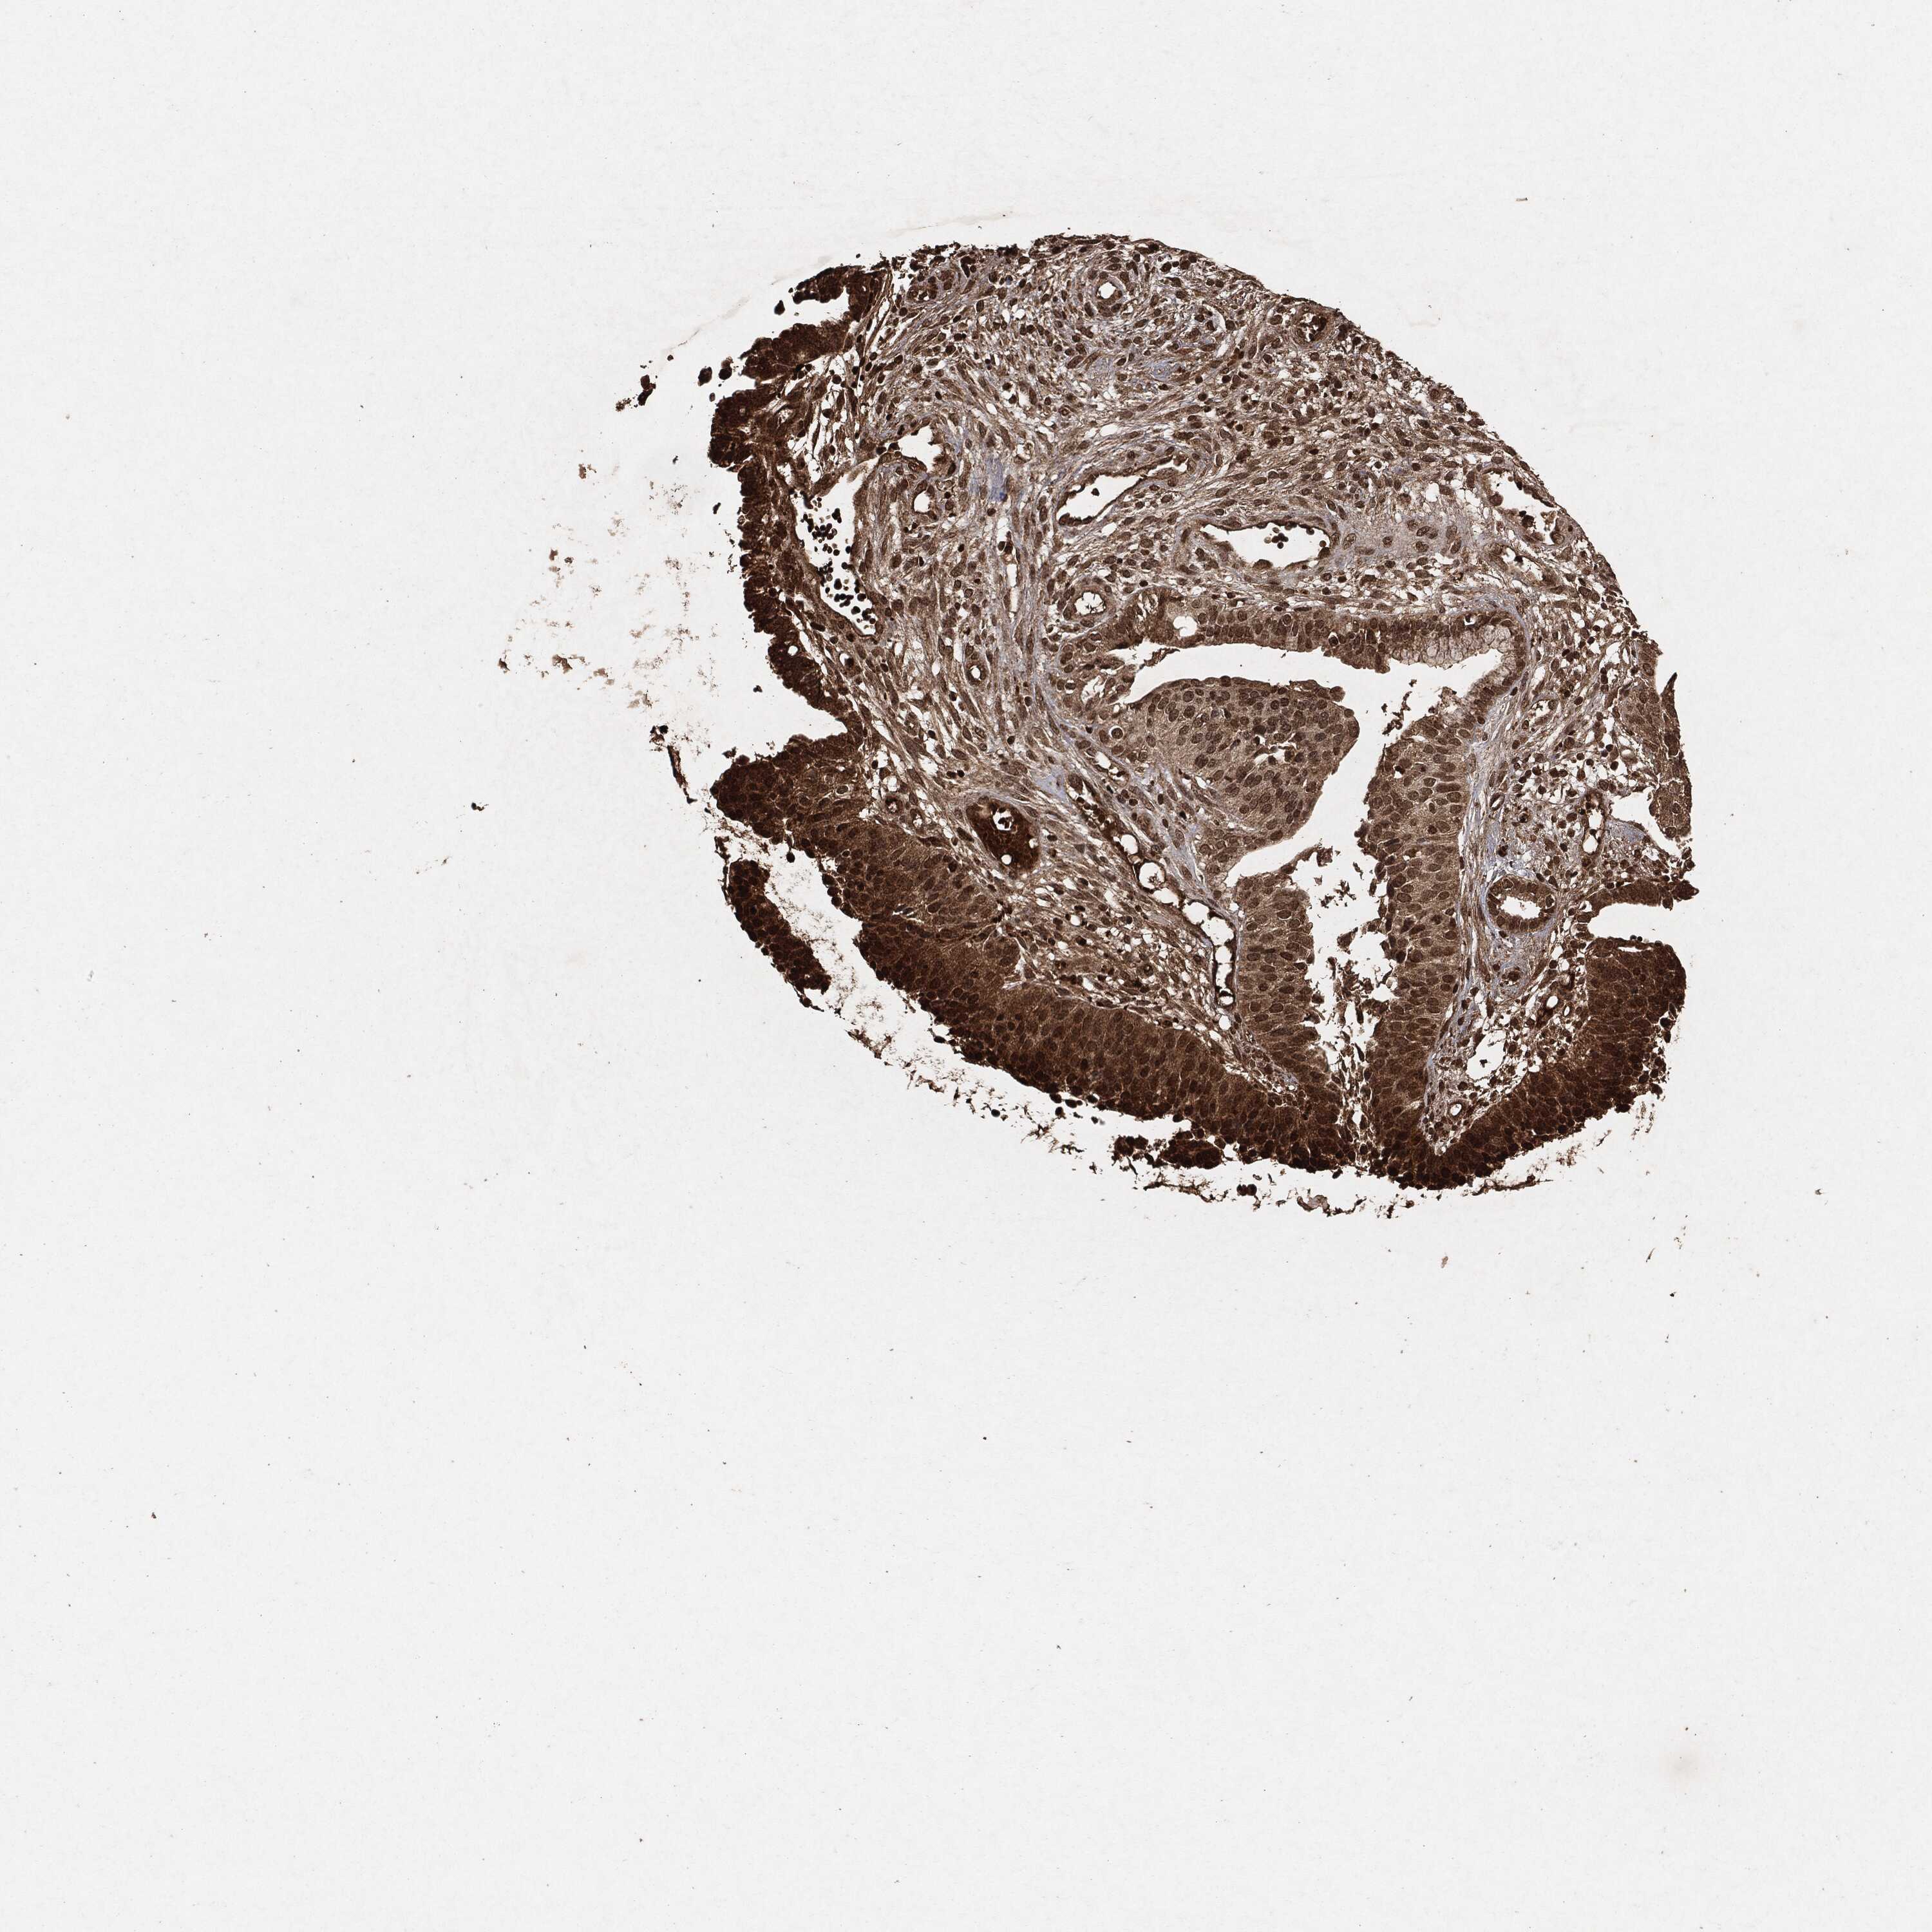

CERVICAL CANCER - Protein expressioni

A mouse-over function shows sample information and annotation data. Click on an image to view it in a full screen mode. Samples can be filtered based on level of antibody staining by selecting one or several of the following categories: high, medium, low and not detected. The assay and annotation is described here.

Note that samples used for immunohistochemistry by the Human Protein Atlas do not correspond to samples in the TCGA dataset.

Antibody stainingi

Antibody staining in the annotated cell types in the current human tissue is reported as not detected, low, medium, or high, based on conventional immunohistochemistry profiling in selected tissues. This score is based on the combination of the staining intensity and fraction of stained cells.

Each image is clickable and will lead to virtual microscopy that enables deeper exploration of all samples and also displays staining intensity scores, fraction scores and subcellular localization as well as patient and tissue information for each sample.